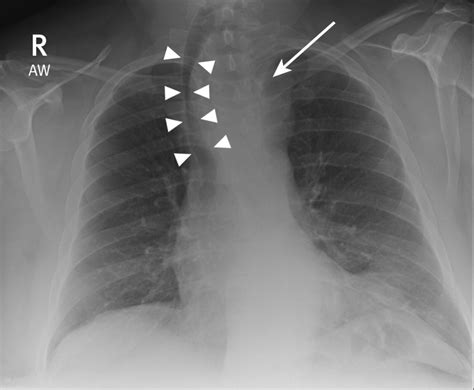

Pneumothorax

Pneumothorax is the presence of air in the pleural space, causing the lung to collapse. It appears as a lucent area without lung markings. Common causes include trauma, spontaneous pneumothorax, and iatrogenic injury.